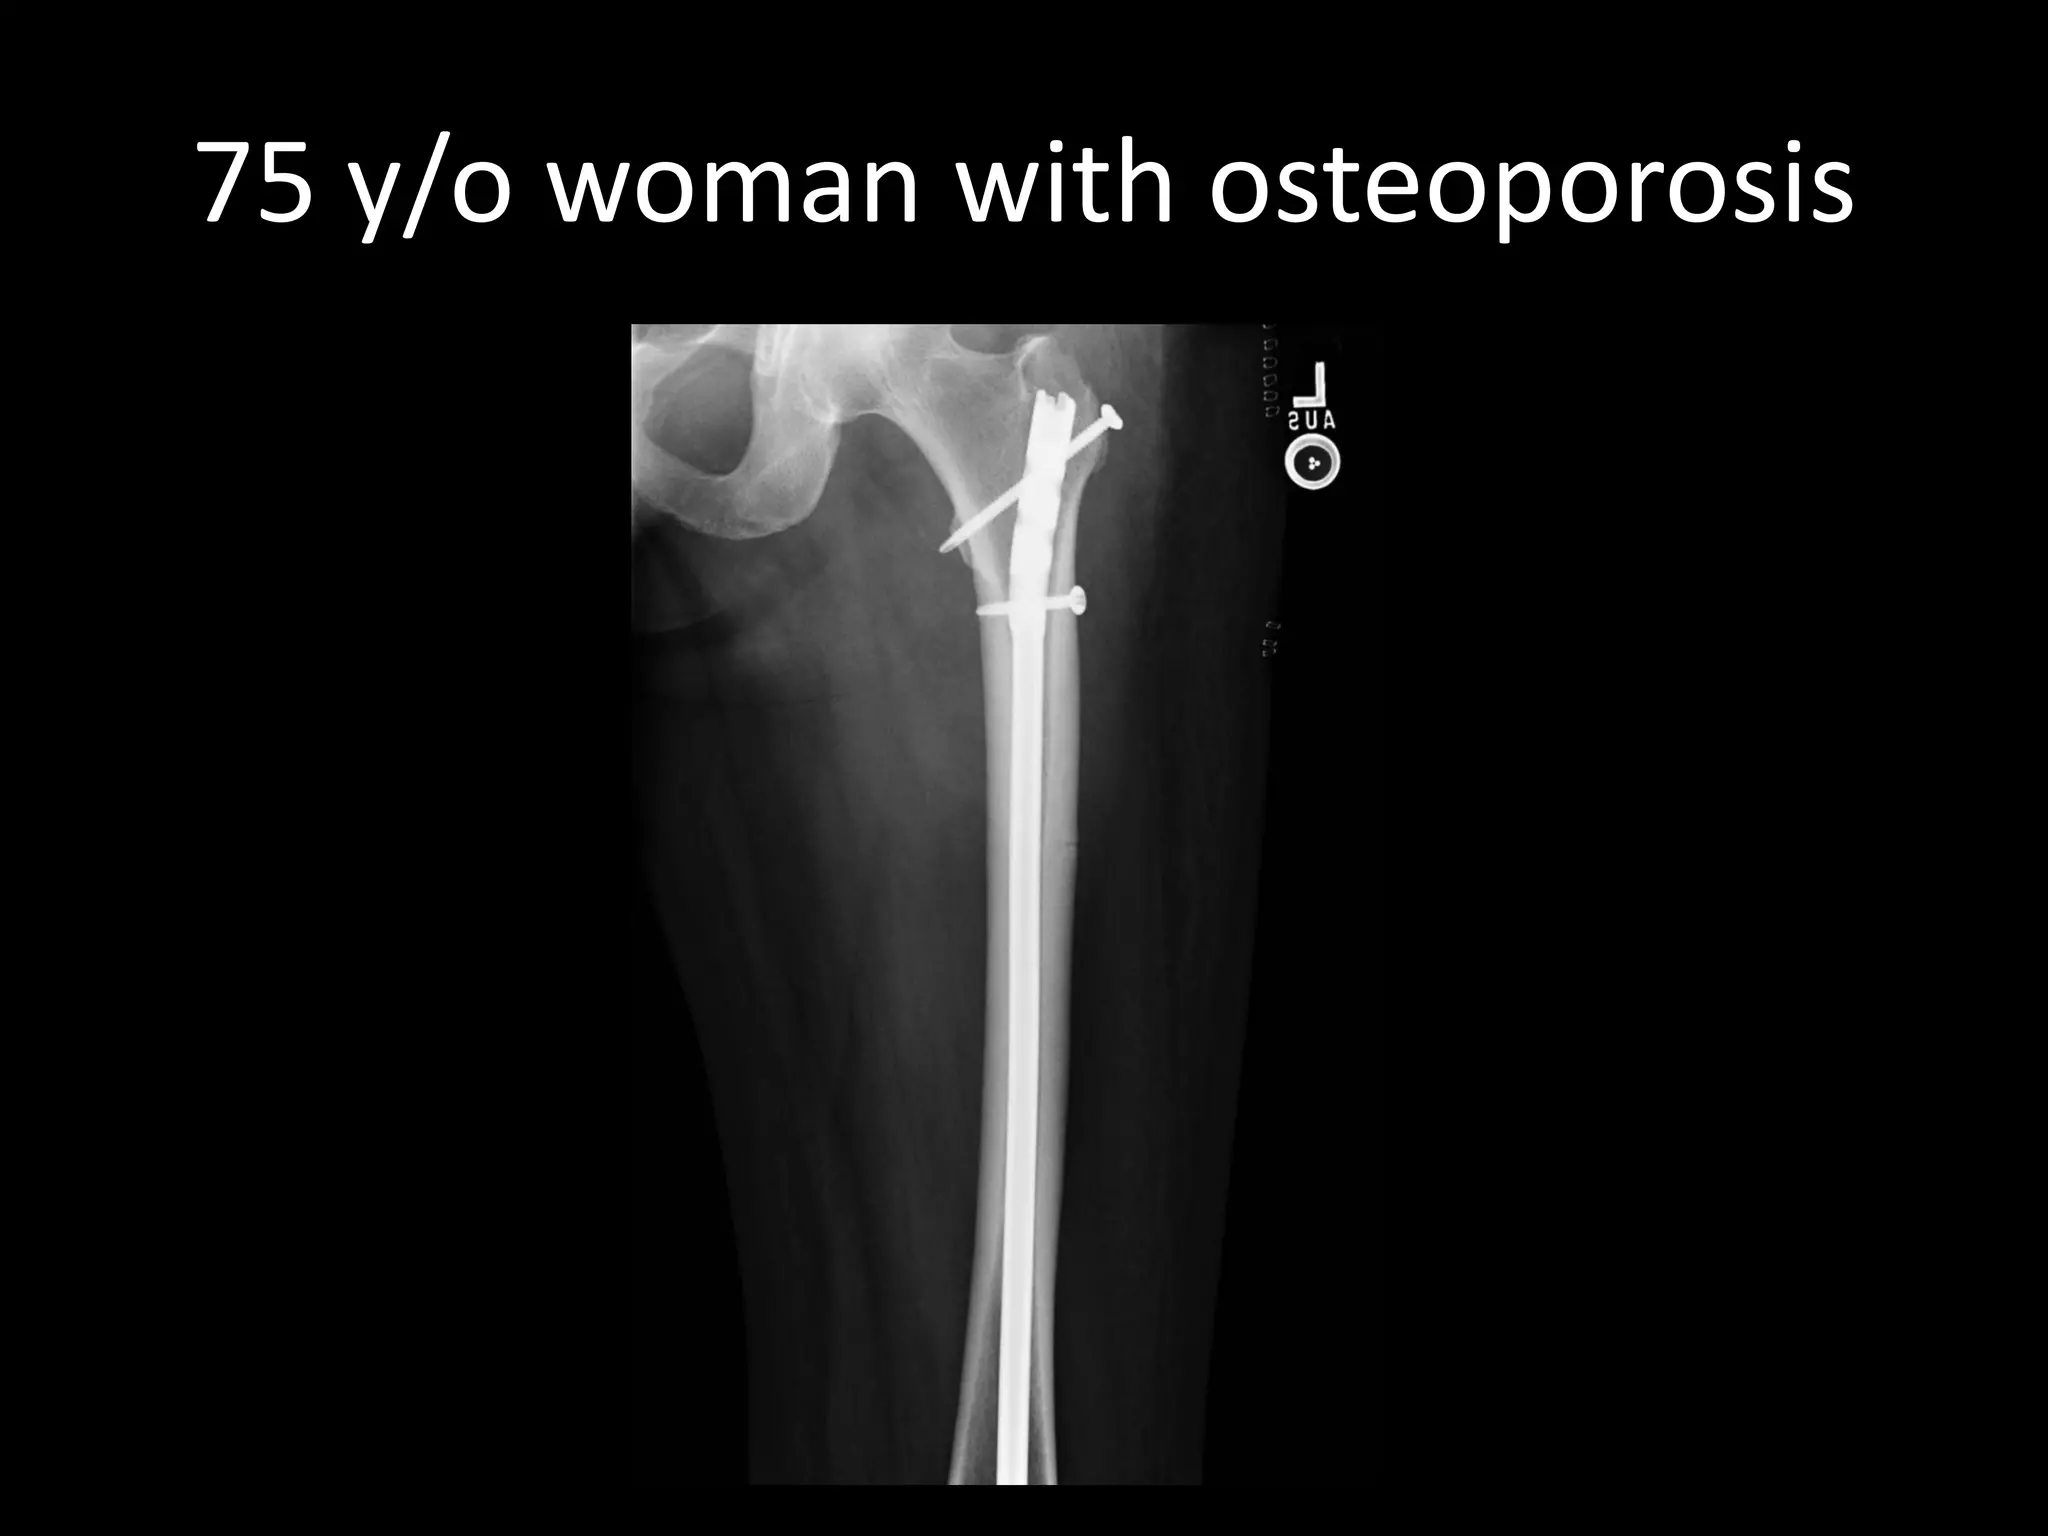

75 y/o woman with osteoporosis

•Long term use of bisphosphonate

•Can also occur without bisphosphonates

•Osteoclast oversuppression → impaired bone remodeling → accumulation of microdamage

•Decreased elasticity, increased brittleness

Atypical femoral fracture

75 y/o womanwith osteoporosis

•Long term useof bisphosphonate •Can also occur without bisphosphonates •Osteoclast oversuppression → impaired bone remodeling → accumulation of microdamage •Decreased elasticity, increased brittleness Atypical femoral fracture